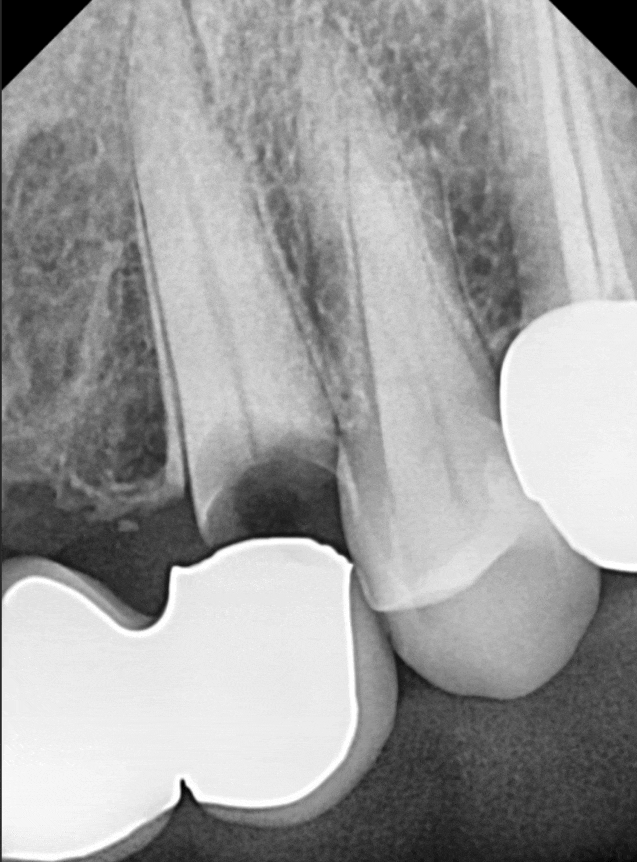

탐침 기구로 체크해 보니,

보철 안쪽으로 기구가 완전히 통과될 정도로

내부 공간이 벌어져 있었는데요~

방사선 사진을 살펴보니 역시나,

2차 충치로 인해 치아 뿌리와 보철물 사이가

완전히 끊어져있네요.. ㅜㅜ

하지만 이 환자분은

가운데 앞니 씌운 곳(#21)이

뿌리 쪽까지 염증이 퍼져 있는 상태였어요.